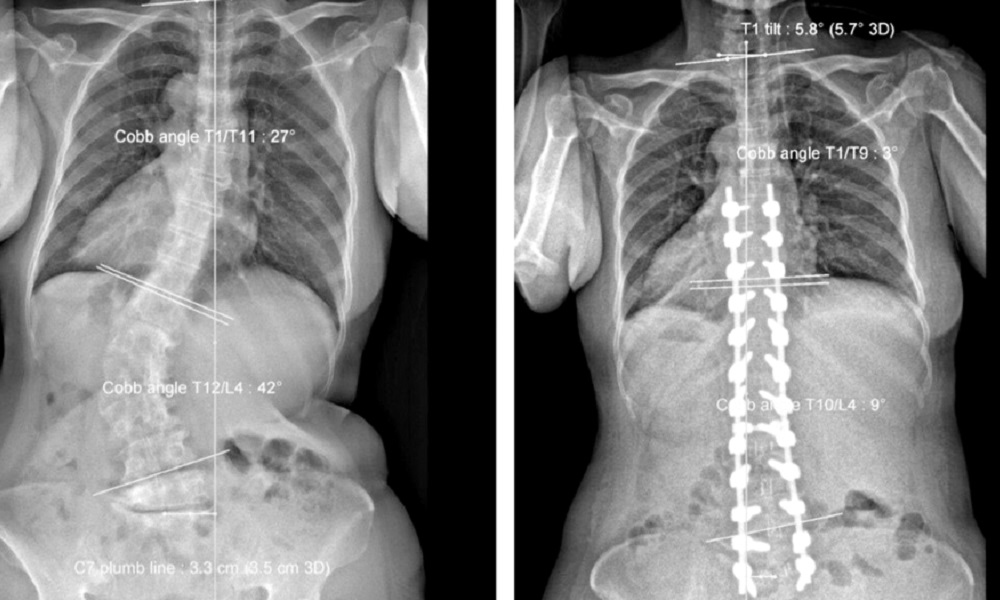

Phẫu thuật chỉnh vẹo cột sống có thể được thực hiện bằng phương pháp mở hoặc phẫu thuật nội soi. Trong quá trình phẫu thuật, các bác sĩ sẽ sử dụng các dụng cụ y tế để nắn chỉnh vị trí của cột sống và gắn các vít nhỏ vào cột sống để giữ vị trí mới.

Sau khi phẫu thuật, bệnh nhân sẽ được theo dõi và điều trị để giảm đau và hỗ trợ phục hồi. Thời gian hồi phục sau phẫu thuật phụ thuộc vào phương pháp phẫu thuật và mức độ nặng của biến dạng vẹo cột sống.

Sau khi xuất viện, bệnh nhân sẽ được theo dõi và điều trị để đảm bảo rằng cột sống đã được nắn chỉnh đúng vị trí và không tái phát biến dạng vẹo cột sống.